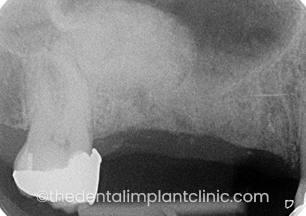

Implant placement to replace missing upper right central incisor tooth (UR1) due to trauma. This patient had a two staged procedure. The first stage involved a block bone graft to regenerate the missing bone ensuring that there was an adequate foundation for the implant to be placed. The second stage involved the placement of the dental implant 9 months after the initial bone grafting procedure had been completed.

Missing UR1 with bone loss due to trauma

Procedures staged: [1] Block bone graft allowing the bone to regenerate for 9 months [2] Implant placement UR1